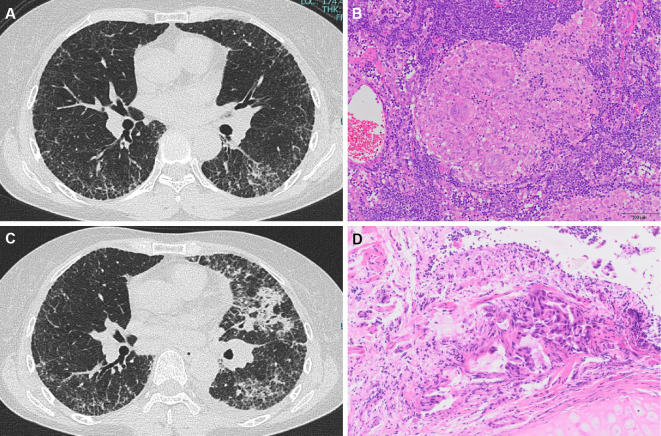

Concurrent Pulmonary Sarcoidosis and Carcinomatous Lymphangitis.

并发肺结节病和癌性淋巴管炎。